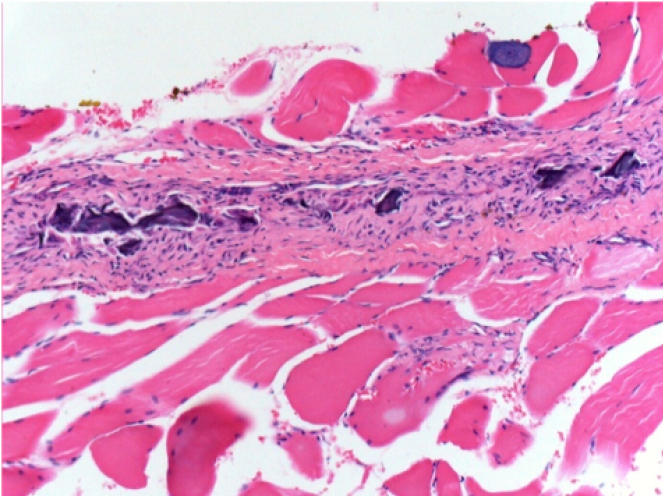

حقن إندوبيل في الأنسجة تحت الجلد

0.5 مل (5 × 0.1 مل) حقن Endopeel SC في المنطقة تحت الجلد اليمنى.

L:200x-Control-SC

R-D10-SC-200X

R-D30-SC-200X

R-D90-SC-200X

R-D210-SC-200X

R-D210-SC-400X